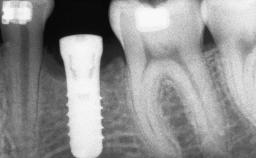

Shell Technique for Horizontal and Vertical Maxillary Bone Augmentation in a Partially Edentulous Patient with Aggressive Periodontal Disease

| # of Implants | 3 |

| Bone Augmentation | Horizontal|Staged|Vertical |